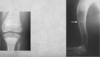

Describe Premature closure of growth plate.

A

e.g. distal ulna such as in image

results in growth discrepancy and may disrupt the function of the joint

What does this depict?

Premature closure of growth plate distal radius.